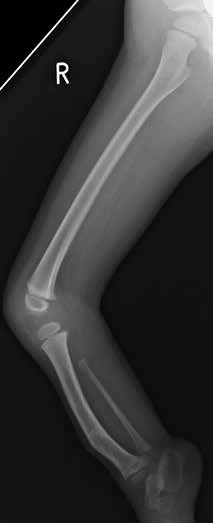

Um ein optimales Bild von der betroffenen Extremität zu gewinnen, sind bildgebende Unterlagen im Rahmen der Befundaufnahme gemeinsam mit dem zuständigen Facharzt zu analysieren. Folgende Deformitätsspektren sind am häufigsten vorhanden und sollten gut dokumentiert werden (Abb. 1 u. 2):

Vorgestellt wird der Fall eines zehnjährigen Patienten mit folgenden Befunden (s. Abb. 1 u. 2):

- Fibuladysplasie rechts

- leicht verkürztes Femur mit minderangelegtem Condylus lateralis

- Dysplasie von ACL und PCL

- verkürzte M. triceps surae und Mm. peronei

- „bowing tibia“

- Valgusstellung des Os calcaneus